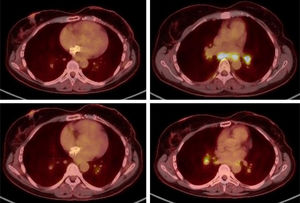

En febrero de 2024 se solicita un PET/TC para control de la enfermedad oncológica y se visualizan múltiples adenopatías hiliomediastínicas con patrón característico de enfermedad inflamatoria granulomatosa (fig. 1). Se realiza broncoscopia con biopsia de dichas adenopatías con hallazgo anatomopatológico de linfadenitis granulomatosa no necrosante (fig. 2), confirmando el diagnóstico de sarcoidosis.

La paciente se encuentra asintomática y sin repercusión clínica a nivel pulmonar, con pruebas funcionales respiratorias normales y manteniendo buena saturación de oxígeno. Por este motivo, se continúa con el tratamiento con capecitabina y se realiza seguimiento activo sin otras medidas terapéuticas adicionales. En la PET/TC de control realizada a los 2 meses se observa disminución global de la intensidad de captación de las adenopatías hiliomediastínicas.

Como única sintomatología en los meses posteriores, la paciente presenta toxicidad plantar. En septiembre de 2024 se detecta elevación de los marcadores tumorales y se confirma progresión tumoral en la PET/TC realizada en octubre de 2024, por lo que se suspende capecitabina. En esta misma prueba, se objetiva total resolución de las adenopatías hiliomediastínicas descritas previamente.